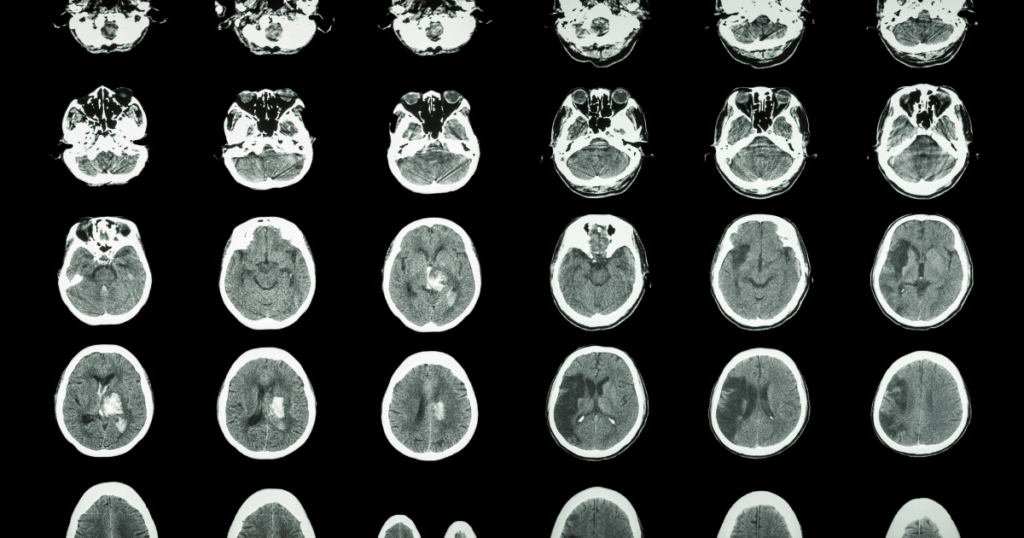

| Stroke diagnostics | 10% |